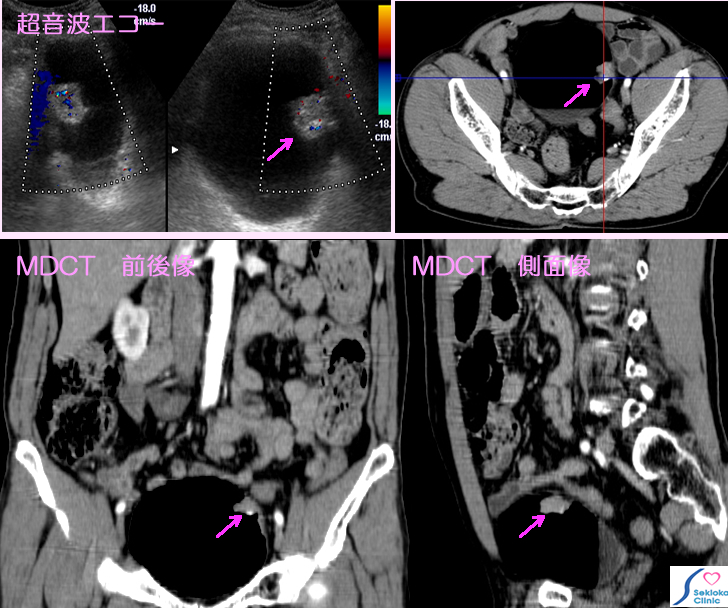

膀胱早期がん

自覚症状

血尿(赤い尿)に気づき来院

診断

超音波エコー検査で膀胱内膜から突出する小腫瘍認め、

造影MDCT検査行う。膀胱壁外への進展の所見認めず、

早期がん と推定される

治療

早期がんであったため、経尿道的切除で膀胱は温存される